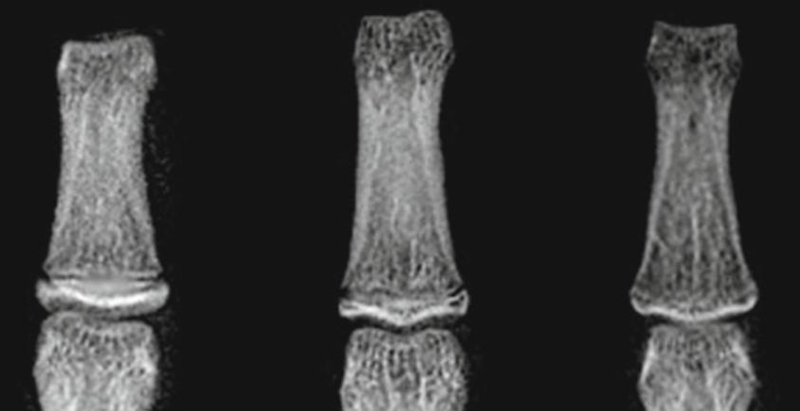

与青春前期类似,这个时期的骨龄评估依然主要是观察指骨骨化中心的宽度与相邻干骺端宽度之间的比较。通常这个时期的骨骺骨化中心的长度要长于相邻干骺端的长度(图7)。

图7 描述了青春早期和中期指骨骨化中心逐渐变宽的过程,最终骨化中心的宽度要大于与其相邻干骺端的宽度